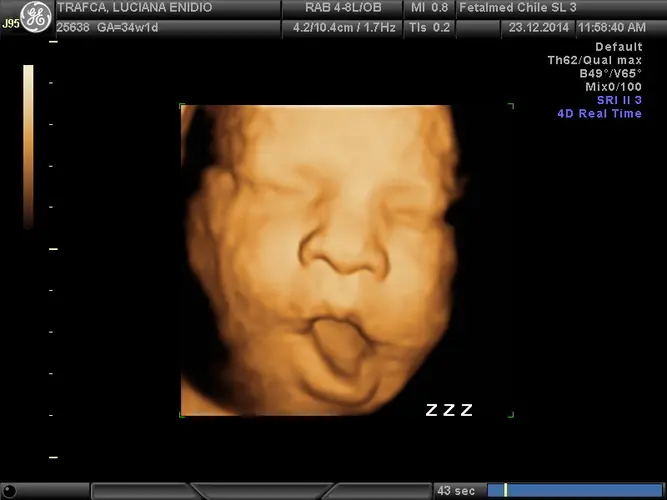

Na 34ª semana de gestação, seu bebê está quase pronto para o mundo exterior! Com aproximadamente 2,3 quilos e entre 43 a 45 centímetros de comprimento, ele agora apresenta comportamentos muito semelhantes aos de um recém-nascido. Seus olhos já abrem e fecham seguindo os ciclos naturais de sono e vigília, demonstrando que seu sistema nervoso está maduro o suficiente para regular essas funções vitais.